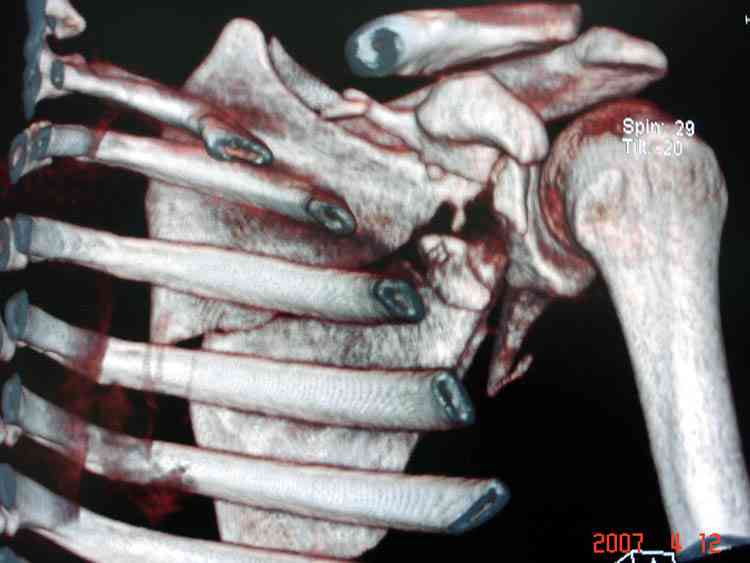

К-томографические и Трехмерные(3D)снимки крайне важны для определения внутрисуставных переломов и классификации.

Нестабильные внесуставные переломы лопатки типично сочетаются с переломами ключицы и ребер.

Сочетания в результате скоростных травм приводят к нестабильности плечевого пояса, и имеют тенденцию ротироваться кнутри, в результате чего возможны повреждения плечевого сплетения.

При отсутствии соединения верхнего пояса с телом из-за перелома ключицы и шейки лопатки имеется состояние "floating shoulder", как в аналогии повреждения около коленного сустава "floating knee" при переломах костей выше и ниже коленного сустава.

В 1993 Goss описал верхне плечевой поддерживающий комплекс (SSSC-superior shoulder suspensory complex), костно-связочное кольцо из акромиона, коракоида, ключицы и гленоида. Повреждения двух или более элементов из перечисленных доказывают наличие флотирования, и рекомендуется операция.